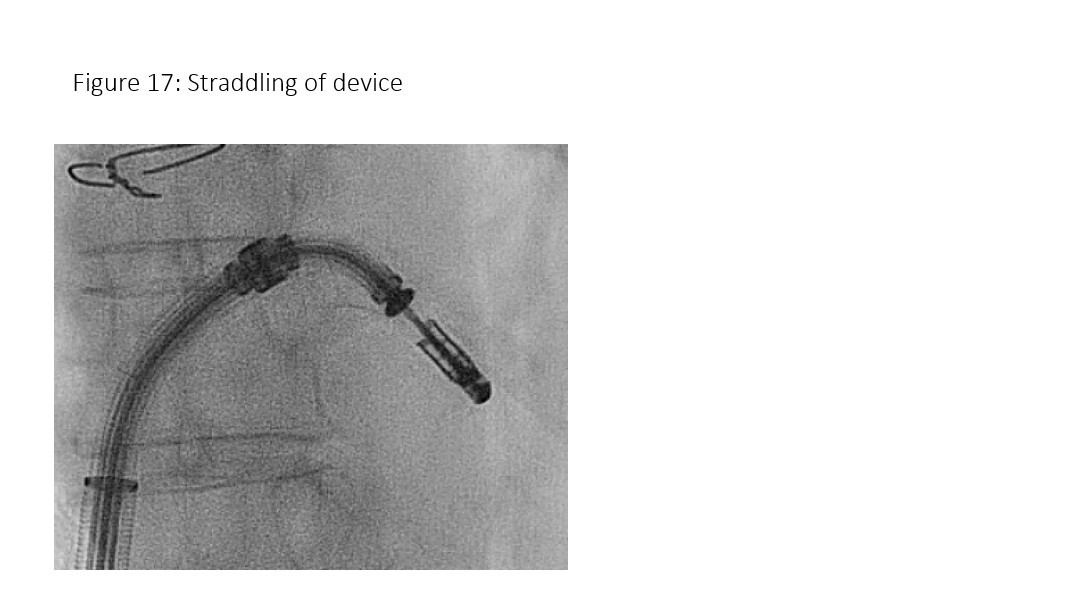

Figure 17: Mitral clip device straddled.

The CDS is advanced via the SGC under fluoroscopic guidance directed toward the left upper pulmonary vein. TEE is necessary to ensure that the tip of the steerable guide catheter remains across the interatrial septum and that the delivery system with the clip at the tip does not cause injury to the free left atrial wall or entering the left atrial appendage (Figure 15). As the CDS carefully exits the sheath it is required that the markers in the system straddle the sheath markers (Figure 16) before the clip can be moved toward the mitral valve. To position the CDS above the MV, a posterior torque of the SGC and simultaneous medial deflection of the CDS accompanied by retraction of the whole system are required. These steps are done under fluoroscopic guidance. After bypassing the pulmonary ridge and the floor of LAA, a gentle anterior rotation of the CDS accompanied with a simple lateral rotation brings the clip above the MV. The aim of this maneuver is to direct the clip in a horizontal direction as seen in the posteroanterior view fluoroscopically.

After straddling the device, bypass the coumadin ridge/LAA via a posterior torque of the SGC and simultaneous medial deflection of the CDS accompanied by retraction of the whole system. These steps are done under fluoroscopic guidance.